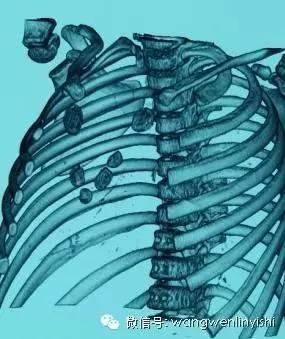

患儿3岁,自幼发现胸骨上半裂开,经检查发现先天性心脏病,室间隔缺损。术前查体发现胸骨上半完全裂开,中间明显凹陷,可以看到心脏搏动。心前区可闻及收缩期杂音。CT检查发现胸骨上半正常结构消失,两侧肋软骨与裂开的胸骨相连。心脏超声提示室间隔缺损。

(三维重建图)